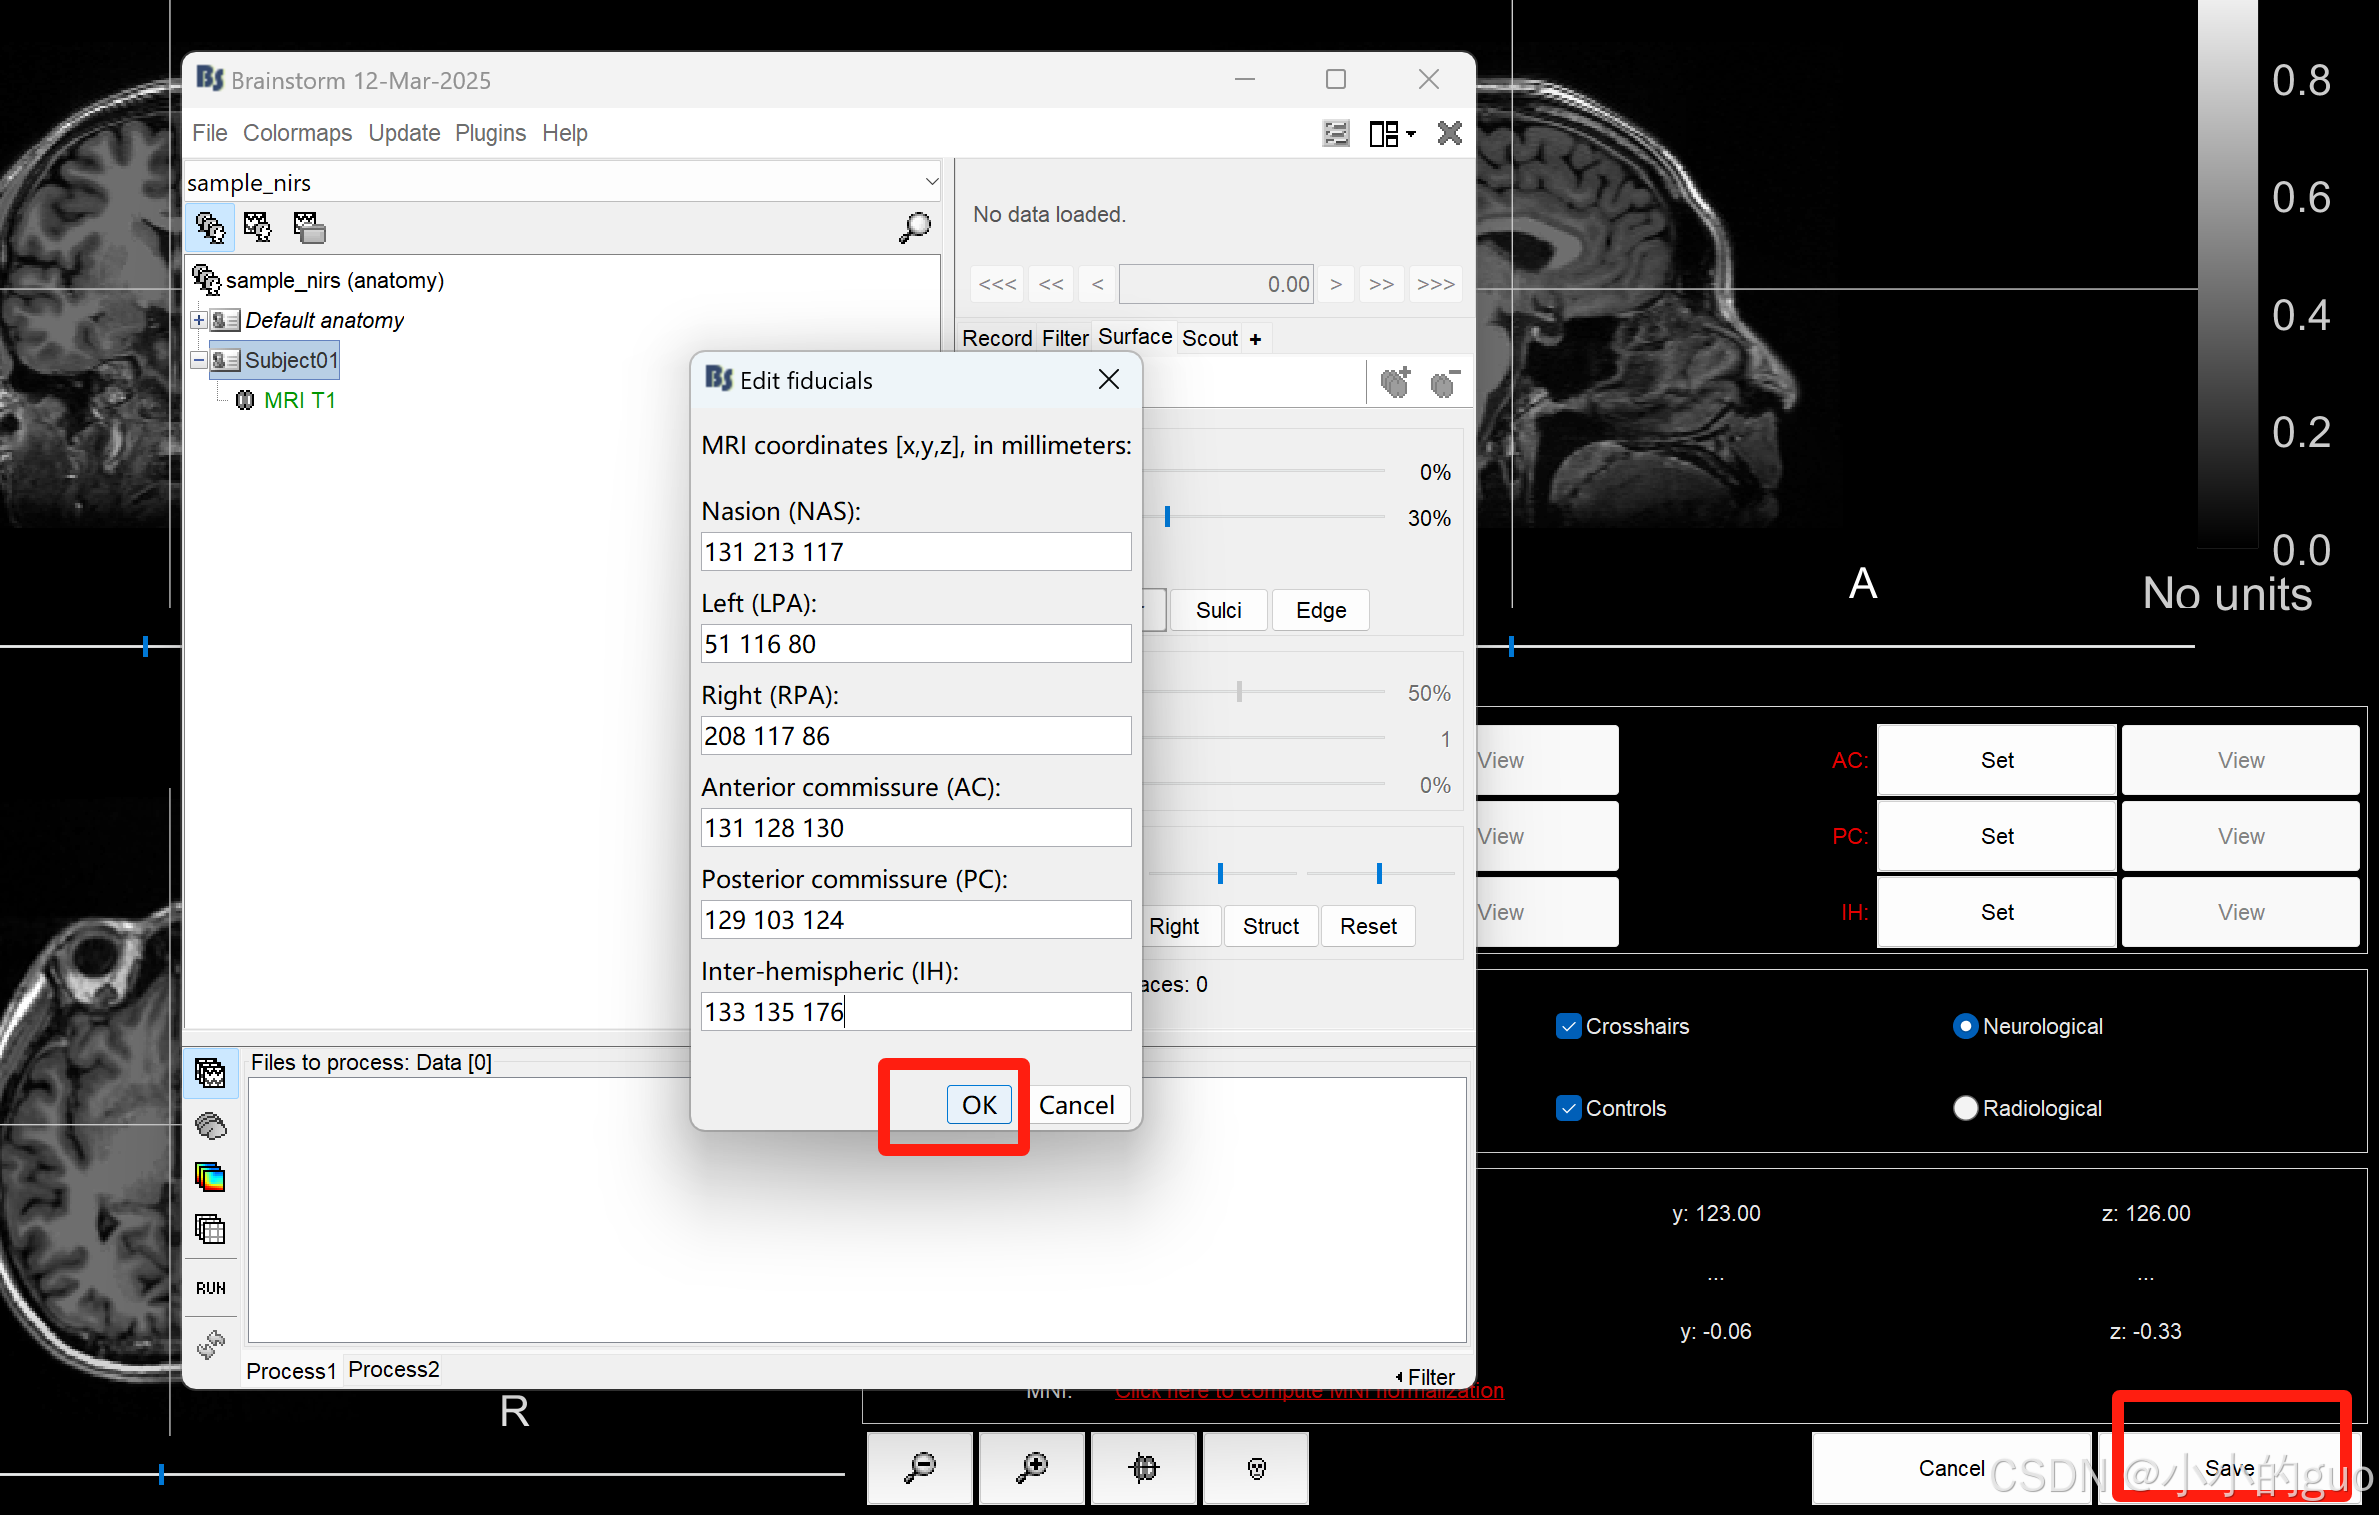

弹出MRI界面,在图像上右键 -> Edit fiducial positions -> MRI coordinates,弹框中输入数值,数值是根据链接1中给出的输入:

点击OK后,可以点击后面Fiducials中的View,查看可定位点,然后点击‘Save’: